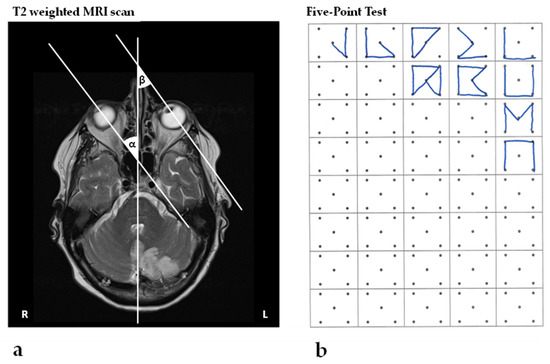

Figure 1.

MRI and the Five-Point Test. (a) T2–weighted contrast MRI images showing a stroke in the left PICA territory one day post-stroke. The neuroimaging of the eye position, by means of the angles formed by the intersection of the ocular axes of the right (α) and left (β) eye and the midline structures of the head, is indicative of spatial neglect, as described by Becker and Karnath [29]; (b) shows the patient’s performance in the Five-Point Test, revealing a significant rightward shift of the spatial distribution of drawn designs 24 days post-stroke (CoC = 0.338; see for example [17]).

The patient found all targets in the Bells Test (CoC = 0), but presented an early orientation towards the right space, i.e., began cancelling targets in the top right corner—a sensitive measure for neglect [20,30]. In the SNT, the patient showed a similar performance: both in the single task (CoC = −0.039) and in the dual task (CoC = 0.012), no spatial bias could be detected, but the patient started in the top right corner. In the Line Bisection Test, the patient performed normally (mean relative deviation of 1.30%). However, in a more demanding assessment—the Five-Point Test—the patient showed clear signs of left-sided neglect, i.e., the spatial distribution of graphical productions was clearly shifted towards the right (CoC = 0.338; Figure 1b).

Interestingly, in the MRI scan performed one day after stroke, the patient’s eye position revealed a significant deviation towards the contralateral side, supporting neglect diagnosis as described by Becker and Karnath [29] (Figure 1a).

One day after stroke, the patient showed a rightward eye deviation in the MRI scan, a clear sign of neglect (Figure 1a; [29]). In the neurorehabilitation unit, twenty-four days post-stroke, the neglect, however, was mild and only detectable when using the sensitive neuropsychological Five-Point Test as well as video-oculography assessment. The patient showed a significant shift in the visual fixation distribution towards the right hemispace (Figure 2a). Furthermore, the first saccade was significantly more often directed towards the right hemispace (Figure 2b).